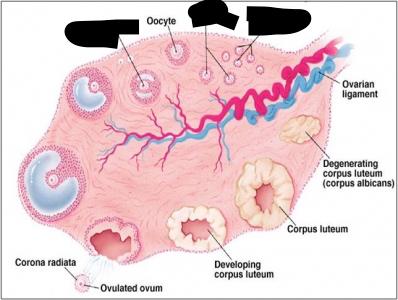

Corpus luteum

Mature (=Graafian, = antral) follicle

Overian ligament

Ovary

Primordial/primary/secondary follicle